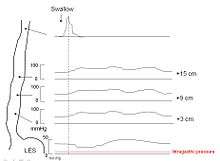

Esophageal manometry

Because of its sensitivity, manometry (esophageal motility study) is considered the key test for establishing the diagnosis. A thin tube is inserted through the nose, and the patient is instructed to swallow several times. The probe measures muscle contractions in different parts of the esophagus during the act of swallowing. Manometry reveals failure of the LES to relax with swallowing and lack of functional peristalsis in the smooth muscle esophagus.[5]

Characteristic manometric findings are:

- Lower esophageal sphincter (LES) fails to relax upon wet swallow (<75% relaxation)

- Pressure of LES <26 mm Hg is normal,>100 is considered achalasia, > 200 is nut cracker achalasia.

- Aperistalsis in esophageal body

- Relative increase in intra-esophageal pressure as compared with intra-gastric pressure